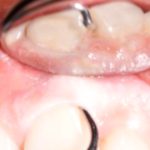

- Clean the inner, outer, top, and bottom surfaces of the teeth, especially the parts around the braces. Make sure to get rid of any small bits of food that might be stuck to them. Those bits can really cause some buildup.

- The wires of your braces should be cleaned with a specialized brush.